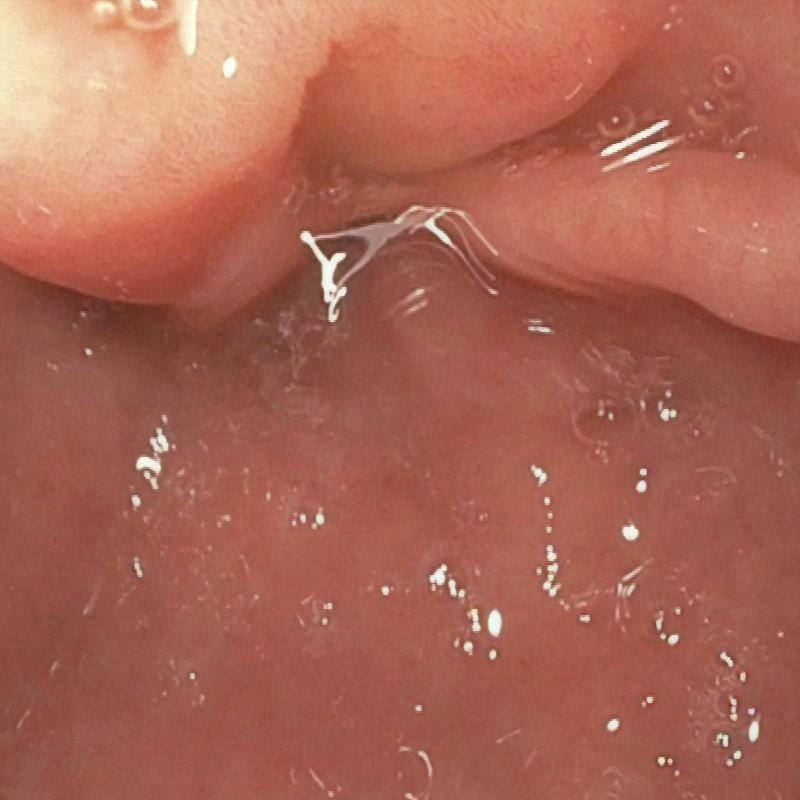

| (a) Input | (b) LIME | (c) HDRNet | (d) LECCM | (e) SwinIR | (f) NAFNet | (g) EndolMLE | (h) Ours | (i) GT |

The proposed method was evaluated on a synthetic dataset. All deep learning-based methods were fine-tuned based on E-kvasri. Figure 2 presents sample results of the proposed method and comparative methods on four endoscopic images from the E-kvasri.